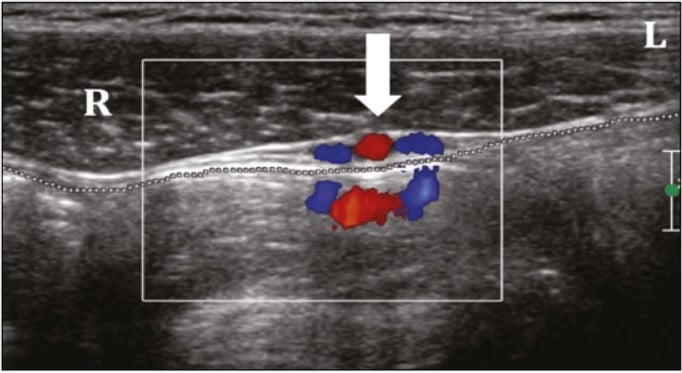

A ultrassonografia com Doppler é a ferramenta diagnóstica de escolha para avaliação da dor inguinoescrotal. Sua alta sensibilidade e especificidade permitem identificar anormalidades estruturais e vasculares. Os principais achados incluem:

- Torção testicular: ausência de fluxo sanguíneo no Doppler colorido, com aumento do volume testicular.

- Orquiepididimite: aumento do fluxo sanguíneo, edema e heterogeneidade testicular.

- Ausência ou redução do fluxo sanguíneo testicular ao Doppler colorido.

A ultrassonografia com Doppler colorido é fundamental para confirmar o diagnóstico de torção testicular. Em casos de torção parcial (menos de 360°), o Doppler espectral auxilia ao detectar uma redução do fluxo diastólico em comparação ao testículo contralateral, sugerindo resistência vascular.

- Fluxo sanguíneo aumentado no Doppler (hiperemia).